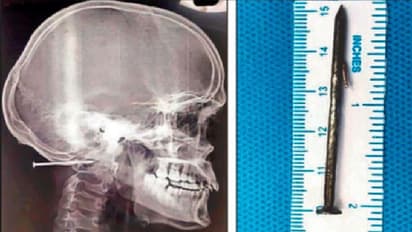

ಚೆನ್ನೈ: ಕೆಲಸದ ವೇಳೆ ಅಚಾನಕ್ ಆಗಿ ಕಾರ್ಮಿಕನ ತಲೆ ಹೊಕ್ಕಿದ್ದ 2 ಇಂಚು ಉದ್ದದ ಮೊಳೆಯೊಂದನ್ನು ವೈದ್ಯರು ಐದು ಗಂಟೆಗಳ ಸುದೀರ್ಘ ಶಸ್ತ್ರಚಿಕಿತ್ಸೆಯ ಬಳಿಕ ಹೊರ ತೆಗೆದಿದ್ದಾರೆ. ಚೆನ್ನೈನ ಖಾಸಗಿ ಆಸ್ಪತ್ರೆಯಲ್ಲಿ ಈ ಶಸ್ತ್ರಚಿಕಿತ್ಸೆ ನಡೆದಿದೆ. ಫ್ಯಾಕ್ಟರಿಯೊಂದರಲ್ಲಿ ಕೆಲಸ ಮಾಡುತ್ತಿದ್ದ 23 ವರ್ಷದ ಕಾರ್ಮಿಕನಿಗೆ ಕೆಲಸ ಮಾಡುತ್ತಿದ್ದ ವೇಳೆ ಅಚಾನಕ್ ಆಗಿ ಮೊಳೆಯೊಂದು ತಲೆ ಹೊಕ್ಕಿದೆ. ಸಹ ಕಾರ್ಮಿಕನ ಮೊಳೆ ಹೊಡೆಯುವ ಗನ್ ಅಚಾನಕ್ ಆಗಿ ಆನ್ ಆದ ಪರಿಣಾಮ ಈ ಘಟನೆ ನಡೆದಿದೆ. ಜುಲೈ 4ರಂದು ಈ ಘಟನೆ ನಡೆದಿದ್ದು, ತಡವಾಗಿ ಬೆಳಕಿಗೆ ಬಂದಿದೆ.

ಜುಲೈ 4 ರಂದು ಚೆನ್ನೈನ (Chennai) ನವಲೂರಿನಲ್ಲಿರುವ ಫ್ಯಾಕ್ಟರಿಯಲ್ಲಿ ಈ ಘಟನೆ ನಡೆದಿದ್ದು, ಬ್ರಹ್ಮನ ಸಹೋದ್ಯೋಗಿ ಮರದ ಬಾಕ್ಸೊಂದನ್ನು ಮೊಳೆ ಹೊಡೆಯುವ ಗನ್ನಿಂದ ಸೀಲ್ ಮಾಡುತ್ತಿದ್ದು, ಈ ವೇಳೆ ಅದೇ ಸ್ಥಳದಲ್ಲಿ ಬ್ರಹ್ಮ ನೆಲಹಾಸನ್ನು ಗುಡಿಸುತ್ತಿದ್ದ, ಈ ವೇಳೆ ಬ್ರಹ್ಮನಿಗೆ ತಲೆಯ ಹಿಂಭಾಗದಲ್ಲಿ ತಡೆದುಕೊಳ್ಳಲಾಗದಷ್ಟು ನೋವಾಗಲಾರಂಭಿಸಿದೆ. ಜೊತೆಗೆ ರಕ್ತಸ್ರಾವವಾಗಲು ಶುರುವಾಗಿದೆ. ಆ ಮಹಡಿಯಲ್ಲಿದ್ದ ಸಿಬ್ಬಂದಿ ಆತನನ್ನು ಸಮಾಧಾನಪಡಿಸಲು ಮುಂದಾಗಿದ್ದಾರೆ. ಆತನ ಕುತ್ತಿಗೆ ಹಾಗೂ ತಲೆಯನ್ನು ಸಂಪರ್ಕಿಸುವ ನಡುವಿನ ಜಾಗದಲ್ಲಿ ಸಣ್ಣ ಬ್ಯಾಟರಿಯಷ್ಟು ಉದ್ದ ಗಾತ್ರದ ಮೊಳೆಯೊಂದು ಸೇರಿಕೊಂಡಿತ್ತು. ಆದರೆ ಈ ನೋವಿನಲ್ಲೂ ಆತನಿಗೆ ಪ್ರಜ್ಞೆ ತಲುಪಿರಲಿಲ್ಲ.

ಆದರೆ ಮೊಳೆ ಆತ ಚರ್ಮದ ಹಂತಕ್ಕಿಂತ ಅರ್ಧ ಇಂಚು ಒಳಗೆ ಕ್ರಾನಿಯೋವರ್ಟೆಬ್ರಲ್ ಜಂಕ್ಷನ್ ಎಂಬ ಸಂಕೀರ್ಣ ಪರಿವರ್ತನೆಯ ವಲಯವನ್ನು (ಕಪಾಲ ಮತ್ತು ಬೆನ್ನುಮೂಳೆಯ ಕೀಲಿನ ನಡುವೆ) ಹೊಕ್ಕಿತ್ತು. ಈ ಸ್ಥಳ ವಿಭಿನ್ನ ಅಂಶಗಳ ಸಂಕೀರ್ಣ ಸಮತೋಲನವನ್ನು ಒಳಗೊಂಡಿದೆ ಮತ್ತು ಎಡ ಕಶೇರುಕ ಅಪಧಮನಿಯ ಹತ್ತಿರದಲ್ಲಿದೆ. ಹೀಗಾಗಿ ಯಾವುದೇ ಅಹಿತಕರ ಸ್ಥಿತಿಗೆ ಇದು ಕಾರಣವಾಗುತ್ತಿತ್ತು. ಒಂದು ಮಾತನಾಡುವುದಕ್ಕೆ ಕಷ್ಟವಾಗುವಂತಹ ಸ್ಥಿತಿ ಉಂಟಾಗುತ್ತಿತ್ತು. ಅಥವಾ ಸಾವಿಗೂ ಕಾರಣವಾಗುತ್ತಿತ್ತು. ಸ್ಕ್ಯಾನಿಂಗ್ ಚಿತ್ರಗಳು ಇದು ಸರಳವಾದ ಮೊಳೆಯಲ್ಲ ಎಂಬುದನ್ನು ತೋರಿಸುತ್ತಿತ್ತು. ಸುಲಭವಾಗಿ ಹೊರಬರಲು ಸಾಧ್ಯವಾಗದಂತ, ಅಥವಾ ಒಮ್ಮೆ ಮರಕ್ಕೆ ಇದನ್ನು ಹೊಡೆದರೆ ಸುಲಭವಾಗಿ ತೆಗೆಯಲಾಗದಂತೆ ಡಿಸೈನ್ ಅನ್ನು ಈ ಮೊಳೆ ಹೊಂದಿತ್ತು ಎಂದು ವೈದ್ಯರಾದ ಅಂಬುಸೆಲ್ವಂ ಹೇಳಿದರು.

ನಂತರ ರೋಗಿಯನ್ನು ಮುಖ ಕೆಳಗೆ ಮಾಡಿ (ಅಂಗಾತ) ಮಲಗಿಸಿ ಶಸ್ತ್ರಚಿಕಿತ್ಸೆ ಮಾಡಲು ನಿರ್ಧರಿಸಲಾಯ್ತು. ಇದಕ್ಕಾಗಿ ವಿಶೇಷವಾದ ಡೈಮಂಡ್ ಬುರ್ ಎಂಬ ನ್ಯೂರೋಸರ್ಜರಿ ಉಪಕರಣ ವನ್ನು ಬಳಸಿ ಮೊಳೆ ಇರುವ ಜಾಗದ ಸುತ್ತ ಡ್ರಿಲ್ (ಕೊರೆಯುವುದು) ಮಾಡಲಾಯಿತು. ನಂತರ ಮೊಳೆಯ ಹಿಡಿತಲೆ ಕಾಣಿಸಿತ್ತು. ನಂತರ ಮತ್ತೆ ಸೂಕ್ಷ್ಮವಾಗಿ ಡ್ರಿಲ್ ಮಾಡಿ ಮೊಳೆಯನ್ನು ಹೊರಗೆಳೆಯಲಾಯಿತು.